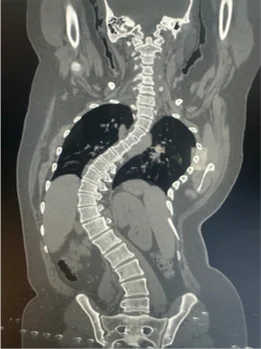

Before & After Clinical Gallery

We showcase real patient cases (with consent), including:

- Pre- and Post-operative MRIs and X-rays

- Disc Herniations, Stenosis, and Spondylolisthesis cases

- Visible improvement in alignment and decompression